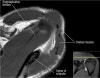

- Coronal section

1) Supraspinatus, Inpraspinatus tendon

2) AC joint

3) Labrum(superior, inferior)

4) Biceps anchor, Inferior GHL, Axillary recess

5) GH joint cartilage

6) Osseous structure

7) Deltoid

Long head 바깥의 고신호는 Biceps groove의 Normal fluid

Acromion의 하면에 부착하는 저신호 : Deltoid tendon or Corocoacromial ligament일수도 있음

Enthesophyte로 오진가능하나 정상 부착부 소견